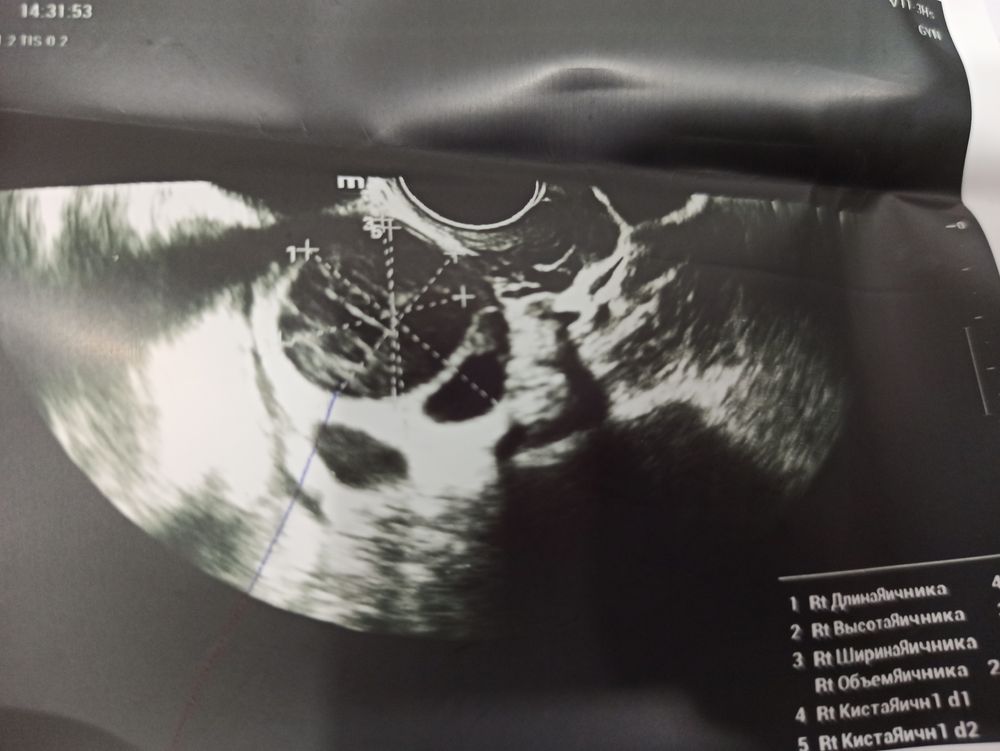

Не могу разобраться,была на узи на 17 Дц. Доктор сказал что овуляции не было, на 14 Ду был супер положительный тест на овуляцию,со всеми как должны быть выделениями яб и ТД.прилагаю фото УЗИ. Мог ли доктор ошибиться? Бывают вообще такие случаи ? Да, и на одном из яичников эндометриозную кисту обнаружили 3 см примерно(((

Оксана , на левом яичники с большей долей вероятности киста эндометриозная, есть утвердительные для этого признаки.

По данным УЗИ, овуляции у Вас не было. На УЗИ на 10 день цикла не определены доминантные фолликулы. Вторичных признаков овуляции и ЖТ не описано. Возможно был персирующий фолликул на правом яичнике, на как таковая овуляция не состоялась.